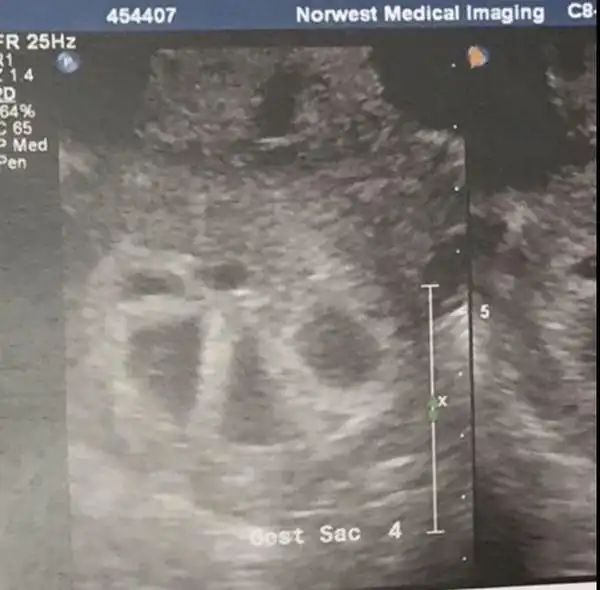

Австралийка Кимберли Туччи и ее муж в течение года не могли забеременеть долгожданным третьим ребенком, а когда это произошло, пара узнала, что у них будут пятерняшки. Шансы зачать пятерняшек составляют один к 55 миллионам, однако, супруги смогли это сделать и теперь готовятся к пополнению.